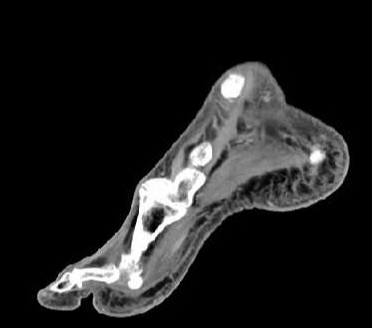

diabetic foot infection treatment and duration for Mild infection moderate to severe infections:

**Mild infections** - if they are infected treat with MRSA and strep coverage can be treated with **empiric short course of 7-14 days of oral antibiotics**: cephalexin, clindamycin, amoxicillin-clavulanate or dicloxacillin Would cultures should be by curettage or biopsy of deep tissue before initiating antiobtics - can also use doxycycline or bactrim. **Severe infections:** - need polymicrobial coverage with staphyloci, streptococci, and aerobic gram negative bacilli and anaerobes **can treat with 2-4 weeks of antibiotics**